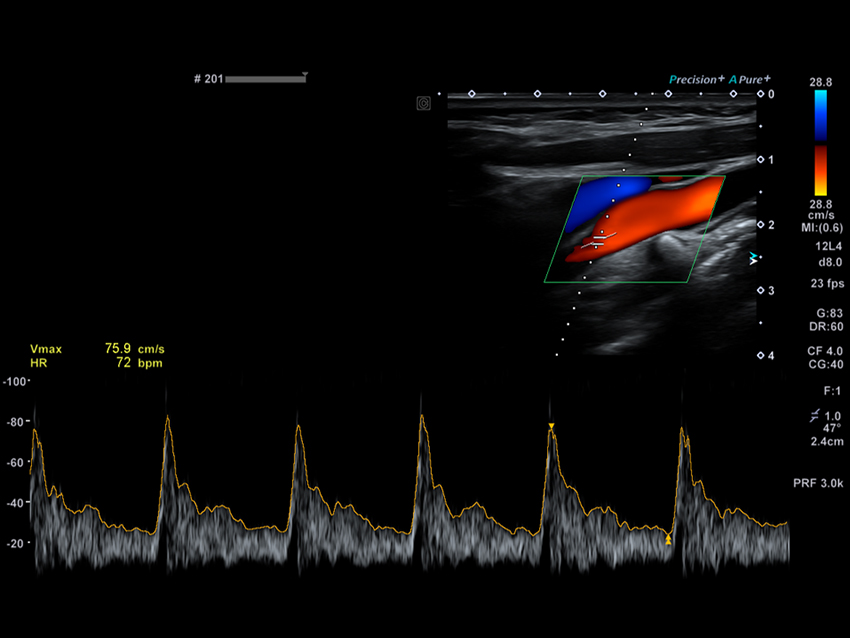

Автоматичне вимірювання комплексу інтима-медіа Auto IMT допомагає підвищити як точність, так і швидкість допплерівських досліджень сонної артерії.

Автоматичне допплерівське стеження спрощує робочий процес за допомогою імпульсно-хвильових допплерівських (PWD) вимірювань.